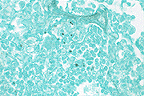

Numerous intracytoplasmic morbilliviral inclusions in the renal pelvic epithelium of a mink. (40X, HE, 64K)

Contributor's Diagnoses and Comments: Renal tubular medullary mineralization, moderate and diffuse. Renal pelvic epithelial apoptosis with intracytoplasmic inclusions. Etiology: canine distemper virus.

Renal tubular mineralization in the medulla is often seen in anorexic mink, probably due to dehydration. Cytoplasmic inclusions were also present in bronchiolar epithelium and in the urinary bladder mucosa. Severe bronchopneumonia was also present. The host range of canine distemper virus includes the dog, coyote, fox, wolf, dingo, jackal, raccoon, panda, weasel, mink, ferret, badger, skunk and otter. It was felt that raccoons may have transmitted the infection to mink in this case. A similar, if not identical virus, has been reported to cause distemper-like illness in captive and wild leopards, tigers, lions, jaguars and civets. Similar viruses infect harbor seals, porpoises and javelinas.

1. Kidney, tubular epithelium and pelvic urothelium: Eosinophilic intracytoplasmic inclusion bodies, with occasional syntical cells, Mustela vison, mustelid, etiology consistent with canine distemper virus.

2. Kidney, corticomedullary junction: Mineralization, tubular epithelium, multifocal, moderate.

3. Kidney, tubular epithelium: Fatty change, diffuse, moderate.

Conference Note: Canine distemper virus (CDV) is a morbillivirus in the Paramyxoviridae family. Infection with CDV occurs by inhalation with the virus localizing in tonsils and bronchial lymph nodes. After 2-5 days there is a cell associated viremia, with the virus infecting lymph nodes, spleen, thymus, bone marrow, and macrophages in the lamina propria of the stomach and intestine. At this stage of infection, severe depletion of lymphocytes may develop with concomitant immunosuppression. At 8-10 days post-infection, the virus again disseminates, with continued infection of mononuclear cells and epithelial cells, causing hyperkeratotic dermatitis, diarrhea, pneumonia, and keratitis. The brain is sometimes affected, usually after the visceral infection has ended. The virus first infects macrophages in the meninges and later spreads to ependymal cells, glial cells, and neurons. Neuronal involvement leads to behavioral changes and varying degrees of muscular spasm or paresis. Forty to sixty days after apparent recovery, some dogs develop demyelinating lesions within the brain. This complication of CDV infection is usually fatal.

Morbilliviruses possess two proteins which facilitate binding to host membranes, hemagglutinin and F protein. The F factor mediates fusion of the viral envelope with the cellular membrane and assists in viral attachment. It also causes host cell fusion and is responsible for the formation of syncytial cells. The ability to fuse host cells allows the virus to spread without being exposed to antibody. To be biologically active the F protein must be cleaved by a host protease into two disulfide-linked polypeptides, F1 and F2. If a host cell lacks the necessary proteases, the virus formed is not infectious, since the F factor is required for viral attachment.

Conference participants also noted numerous lipid vacuoles within the renal tubular epithelium. This is a common finding in anorectic or fasted mustelids and is related to the high metabolic rate of these animals and their ability to rapidly mobilize fat stores.